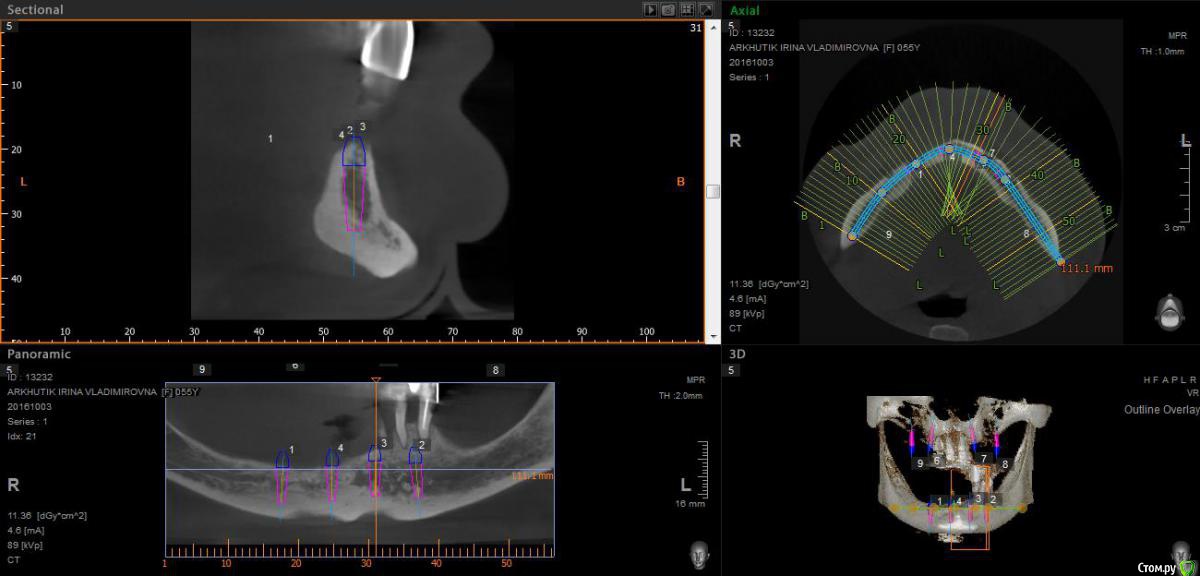

Rusty Опубликовано 5 октября, 2016 Поделиться Опубликовано 5 октября, 2016 Добрый день. К ортопеду обратилась пациентка 55-60 лет с такой ситуацией. Пришла с дочкой, дочь с мамой настаивали на несьемной конструкции, ортопед отправил на кт и вот. Не хочу планировать ей много хирургии, оцените и мой план пожалуйста и буду рад услышать советы по реабилитации пациента. По сути да) просто искал место куда есть возможность поставить, ортопед говорит тогда балка либо локаторы Ссылка на комментарий

Nazim_NV86 Опубликовано 5 октября, 2016 Поделиться Опубликовано 5 октября, 2016 На н/ч балка? Какие измерения в дист отделах? На в/ч мало четырёх. По три бы. Ссылка на комментарий

Rusty Опубликовано 5 октября, 2016 Автор Поделиться Опубликовано 5 октября, 2016 На н/ч балка? Какие измерения в дист отделах? На в/ч мало четырёх. По три бы.На н/ч балка, в дистальных отделах над каналом около 3мм. На вч условий для установки больше 4 не нашел) Ссылка на комментарий

Nazim_NV86 Опубликовано 6 октября, 2016 Поделиться Опубликовано 6 октября, 2016 Попробуйте на вч поискать ещё возможность хотя бы по Палаччи поставить. Ссылка на комментарий